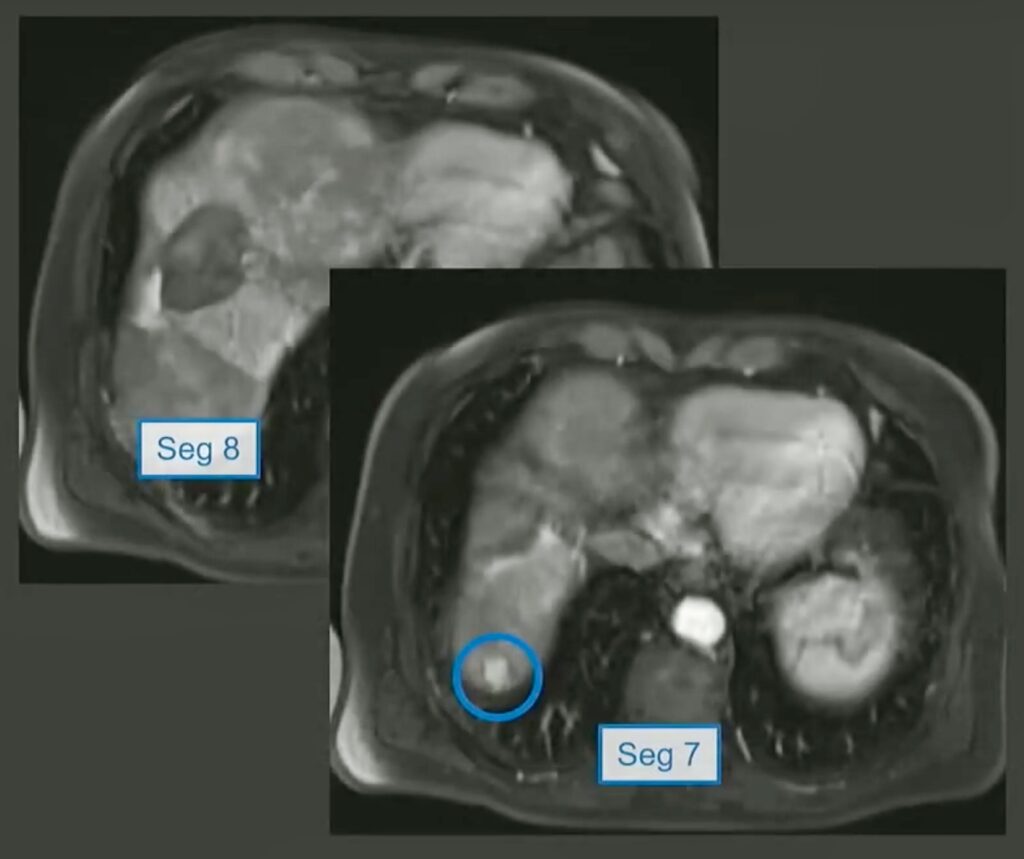

The Patient: During his Vascular/Interventional Case Review from the ARRS Annual Meeting, Dr. Aaltonen introduced us to a 68-year-old male with HCC, post-TACE x2, who presented with a new segment 7 lesion at the hepatic dome.

The Question: Given the obstructions, which approach would work best for microwave ablation (MWA)?